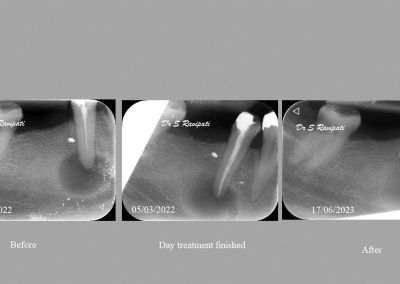

During the consultation, the dentist will first listen to your concerns and carry out appropriate tests to identify the right tooth that is causing pain. As a part of the diagnosis, your dentist will carry out various clinical tests to identify the right tooth and will take some radiographs which can aid in the diagnosis.

Before commencing the treatment, a local anaesthetic is administered and later a protective non-latex rubber sheet is placed around the tooth to prevent saliva contaminating the tooth and at the same time improves patients comfort.

An access cavity is placed on the surface where the patient bites, to reach the root canals of the tooth. Once all the canals are identified, small files are used to remove the infected pulp.

Files of different sizes are used to eliminate bacteria and infection and to shape the canals. The canals are disinfected thoroughly with irrigants and later the canals will be sealed in 3 dimensions with a special medicament called gutta-percha to prevent reinfection of the tooth and the access cavity will be sealed with a temporary filling.